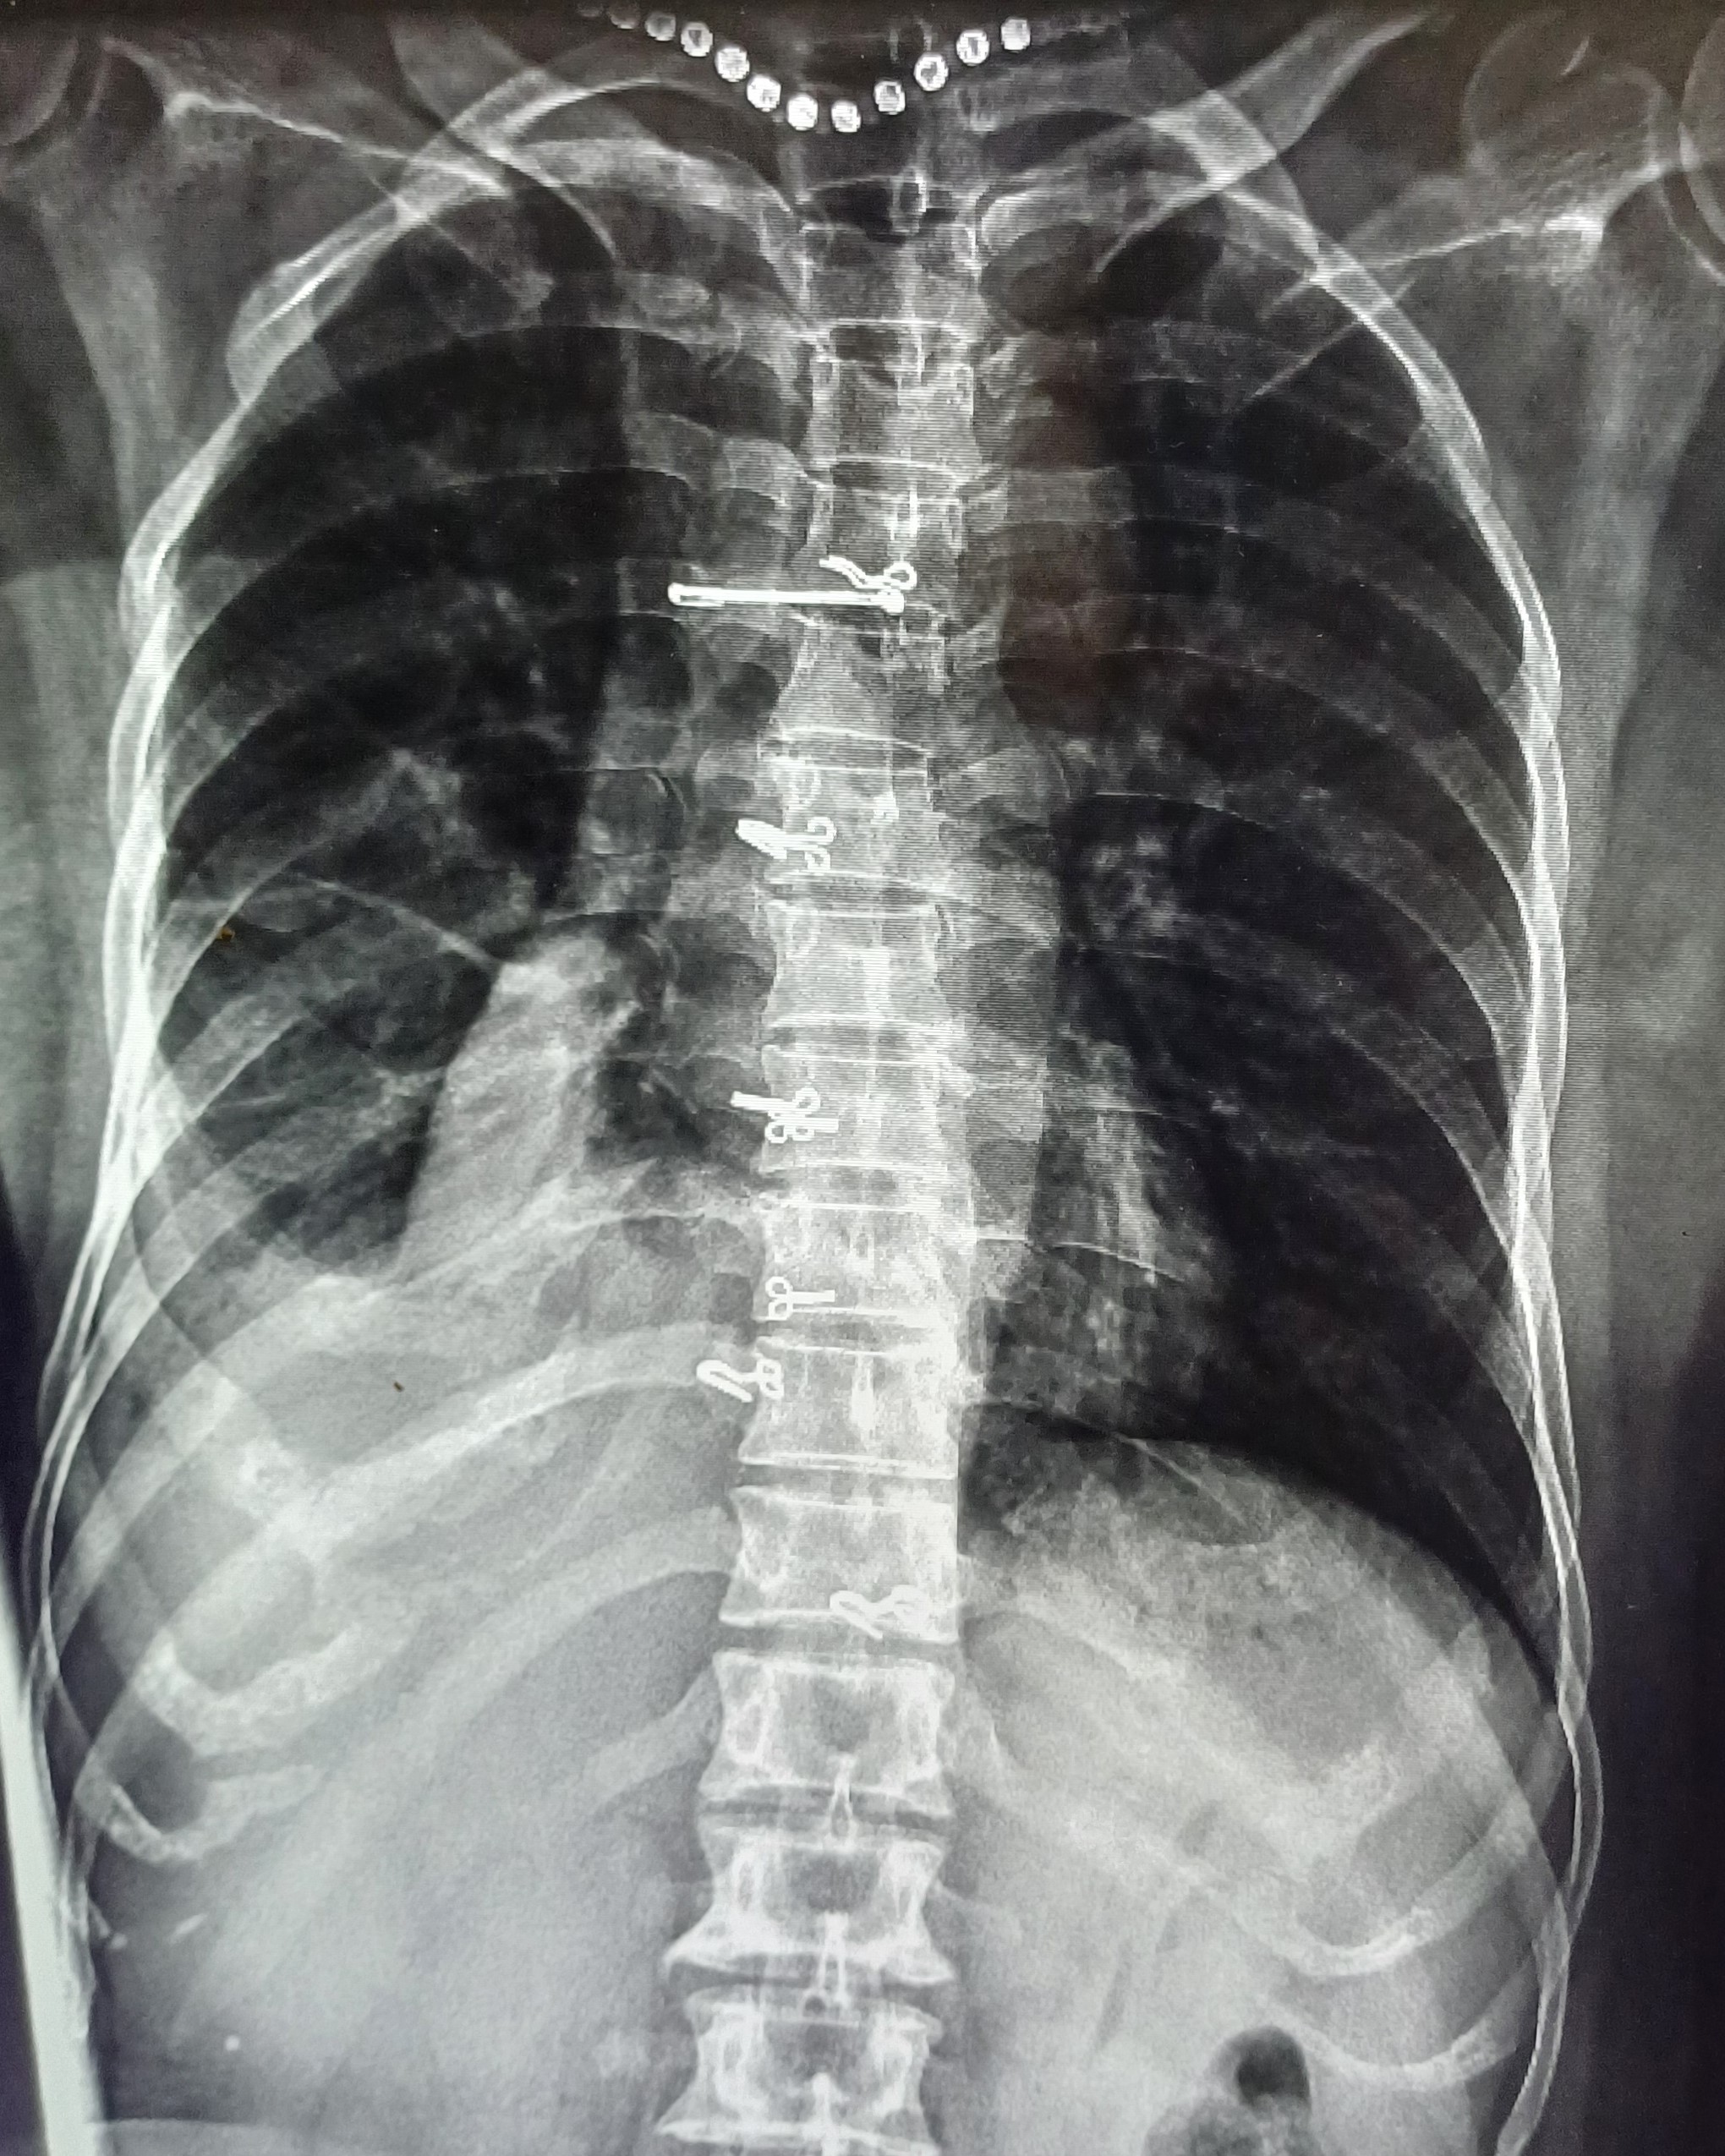

| 7 | IGGMC, Nagpur, Nagpur | P2 | 29-4465 | Ibrahim Pathan | Consent taken on Paper | 21 Yrs. |

Provisional Diag : Pleural Effusion ?

Final Diag : Tubercular Pleural effusion (Clinically Diagnosed Tubercular Pleural effusion) |

TB Case (Confirmed) | Right sided pleural effusion | Abnormality visible on x-ray |